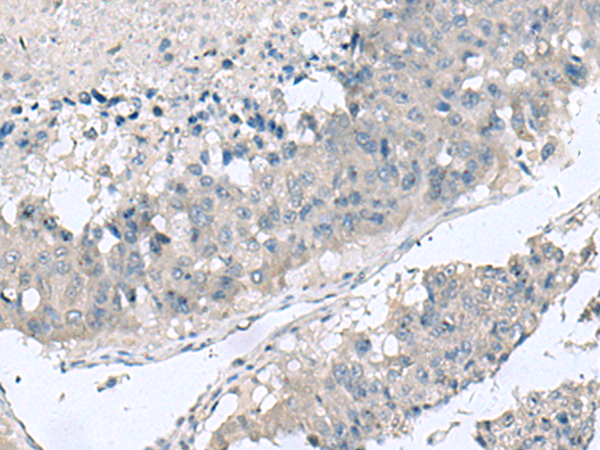

IHC positive control: |

Human colorectal cancerHuman liver cancer |

IHC Recommend dilution: |

20-100 |